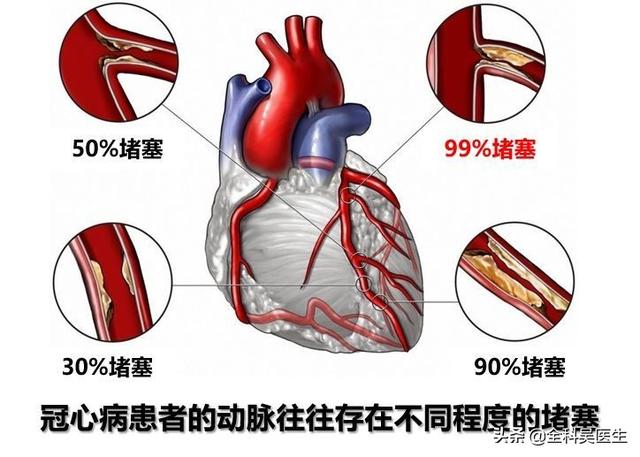

冠状動脈性心臓病は、私たちの生活で最も一般的な心臓病であり、死亡率は非常に高く、冠状動脈性心臓病患者の約30%から60%が突然死に至る。過去には、冠状動脈性心臓病は中高年の病気だと言われていたが、過去30年間で、冠状動脈性心臓病の発生率は明らかに増加傾向にあり、近年では、圧力の生活と仕事が増加し続けているため、ほとんど毎日冠状動脈性心臓病のために突然死があり、突然死はますます多くなっている。ますます多くの若者が。

私たちは皆、多かれ少なかれ知っているはずだ。冠状動脈性心臓病とは、主に心臓の冠状動脈が狭くなる病気である。心臓に血液を供給する血管の狭窄は、心筋虚血や心筋壊死を引き起こす可能性があり、この狭窄を解消して冠動脈への血液供給を回復させるために、治療法のひとつは次のようなものである。何か支えとなるものを持っていく。それこそが、今、私たちが話しているブラケットなのだ。

まず、冠動脈性心疾患とはどんな病気なのかを見てみよう。その名の通り冠動脈疾患は、心臓の "エンジン "に血液を供給する冠動脈に問題がある病気である。。

通常、人が安静にしているときの冠動脈の血流量は毎分250ml程度で、これは心臓全体の血液量の5%に相当する。そして心筋の酸素摂取量は比較的一定である。1000mlの冠動脈血流からの酸素摂取量は約150mlである。肉体労働に従事したり、感情的に興奮したりすると、心臓は心拍数を増やし、収縮力が高まり、その結果心筋の酸素需要が増大し、冠動脈は心筋の酸素需要を満たすために血流量を増やす。

でもね。もし冠動脈の内腔が狭くなっていれば、心筋の酸素需要が増大しても、冠動脈の血液供給はそれに応じて増大することができず、心筋虚血となり、心筋虚血が長引くと心筋壊死を引き起こし、心臓発作の引き金となる。急性心筋梗塞は、不整脈、心原性ショック、心不全、心室壁破裂などの重篤な結果をもたらすこともあるので、冠動脈性心疾患は非常に深刻に受け止めなければならない。

冠状動脈は心臓に血液を供給する主な動脈で、年齢、三高、慢性病、悪習慣などの影響を受けて、心臓に血液を供給する冠状動脈も他の動脈と同じように、アテローム性動脈硬化症、狭窄、プラークなどの問題が現れる、冠状動脈の狭窄が50%以上の場合、通常、心臓の血液供給と酸素供給が大きな影響を受けると考えられ、このような場合、冠状動脈性心臓病と診断することができます。このような場合、冠動脈性心疾患と診断することができる。

冠動脈の動脈硬化の程度が異なれば、冠動脈疾患の治療法も異なる。 労作狭心症程度の冠動脈狭窄の患者や、薬理学的介入で症状が確実に緩和される冠動脈疾患の患者など、それほど重篤でない冠動脈狭窄の患者に対しては、一般にステント留置術は必要ないが、次の2つのシナリオの場合には、医師は患者にステント留置術を検討するよう勧める。冠動脈疾患のインターベンション治療

(1) 冠動脈:冠動脈は心臓、すなわち心筋そのものに血液を供給する動脈である。 冠動脈には3本の太い幹があり、それが次第にさまざまな枝に漸増し、最終的には心臓と心筋組織全体に密な魚網を形成する。冠動脈疾患病変の大部分はこの3本の太い幹にあり、枝分かれの第一段階である小枝の病変は比較的小さい。臨床用語で "3枝病変 "とは、右冠動脈、前下行枝、エコー源性枝の3つの主幹を指す。

(2) 動脈硬化:冠動脈性心疾患とは、血液中の脂質成分が内皮細胞の下に侵入し、炎症反応が起こり、動脈硬化性プラークが形成されることによって引き起こされる病気のことである。

(3) 心臓病:人がある年齢に達すると、実際、全身の多くの血管が動脈硬化を起こす可能性があるが、動脈硬化の狭窄がある程度に達した場合のみ、対応する臓器に明らかな影響を引き起こす。例えば、冠状動脈硬化症は、内腔の狭窄が50%以上であれば、冠状動脈硬化性心疾患と呼ぶことができ、心臓の機能に影響を与えるが、50%未満であれば、冠状動脈硬化症と呼ぶ。

前述したように、50%以上の冠動脈狭窄は冠動脈血流により顕著な影響を与える可能性があり、狭心症のような心筋への血液供給不足の症状によって証明される。この病態は、積極的な薬物治療と生活習慣の改善を行えば、増悪することなく数年間安定していることがあり、これが安定狭心症である。冠動脈の狭窄が75-80%以下であれば、積極的な治療により心筋梗塞を起こす可能性は低くなる。また、冠動脈狭窄の進行が緩徐であるため、体が適応して側副血行路が形成されるのに十分な時間があり(側副血行路から血液が供給される)、体に明らかな違和感がないため、保存的治療の継続を考慮できる患者もいる。もちろん、個々の患者には、年齢、心電図検査、冠動脈造影の状態、症状など、考慮すべき要素がもっとある。

- 冠動脈は、心臓そのものに血液を供給する動脈であり、動脈硬化、または私たちがよく呼ぶプラークである。冠動脈はプラークを生成し、プラークは徐々に大きくなり、心臓への血液と酸素が不足し、さまざまな症状を引き起こす。

一般に、冠動脈を塞いでいるプラークが50%以下であれば、冠動脈性心臓病とは呼ばず、冠動脈硬化症と呼び、現時点では比較的軽症であるが、将来的にはより危険である。

- それとともにプラークは徐々に大きくなり、冠動脈狭窄が50%を超えると冠動脈疾患と呼ばれ始める。

- 冠動脈の狭窄が50~70%以上になると、狭心症の症状が現れることがある。穏やかな状態では、患者は症状がないかもしれませんが、感情的な興奮、活動状況、心臓の酸素需要が増加すると、冠動脈は、狭窄のため、十分な酸素を供給することができません、この場合、血液不足、酸素不足のため、心臓は胸の締め付け感、前胸部痛の症状が現れます。これが安定狭心症です。

- 狭窄が90%以上などさらに悪化すると、少し動いただけで狭心症が起こるようになり、薬物療法も効かなくなる。この場合、心臓ステント留置術を選択し、狭窄を開いた状態に保持することで、症状が大幅に緩和される。

冠動脈性心疾患とは、冠動脈アテローム性動脈硬化性心疾患の略称であり、主に心臓に血液を供給する動脈である冠動脈のアテローム性動脈硬化によって引き起こされる。動脈にアテローム性動脈硬化症が起こると、動脈の内表面にプラークが形成され、プラークが蓄積するほど動脈の直径が狭くなる。狭窄の程度が50%未満であれば、心筋への血液供給には影響しないので、一般的に症状はありませんが、50%以上になると、心筋への血液供給に影響を及ぼし、心筋の酸素消費量が増加しても、心筋が十分な酸素を得ることができず、心筋虚血、低酸素状態になると、胸部圧迫感、胸痛の症状が誘発され、これを狭心症と呼びますが、狭心症の症状は活動を停止すると徐々に緩和されます。狭窄の程度がさらに悪化したり、局所的なプラークの破裂、冠動脈の血栓閉塞によって心筋虚血が生じたりすると、狭心症の程度はさらに悪化し、緩和されない状態が続き、閉塞が解除されなければ心筋虚血壊死を引き起こし、ついには患者の突然死に至ることもあり、これが心筋梗塞と呼ばれるものです!

冠動脈疾患の治療には、薬物療法、ステント、バイパス移植の3つがある。一般的には、冠動脈の狭窄が70パーセントを超えると、狭窄した血管を開くためにステントを留置する必要がある。つまり、ステント留置の基準を満たす冠動脈疾患とは、冠動脈の狭窄が重症化し、いつ心筋梗塞を起こしてもおかしくない状態であり、そうでなければ冠動脈ステントを留置する必要はないということである。とはいえ、心臓ステントは重大な病気だと思いますか?